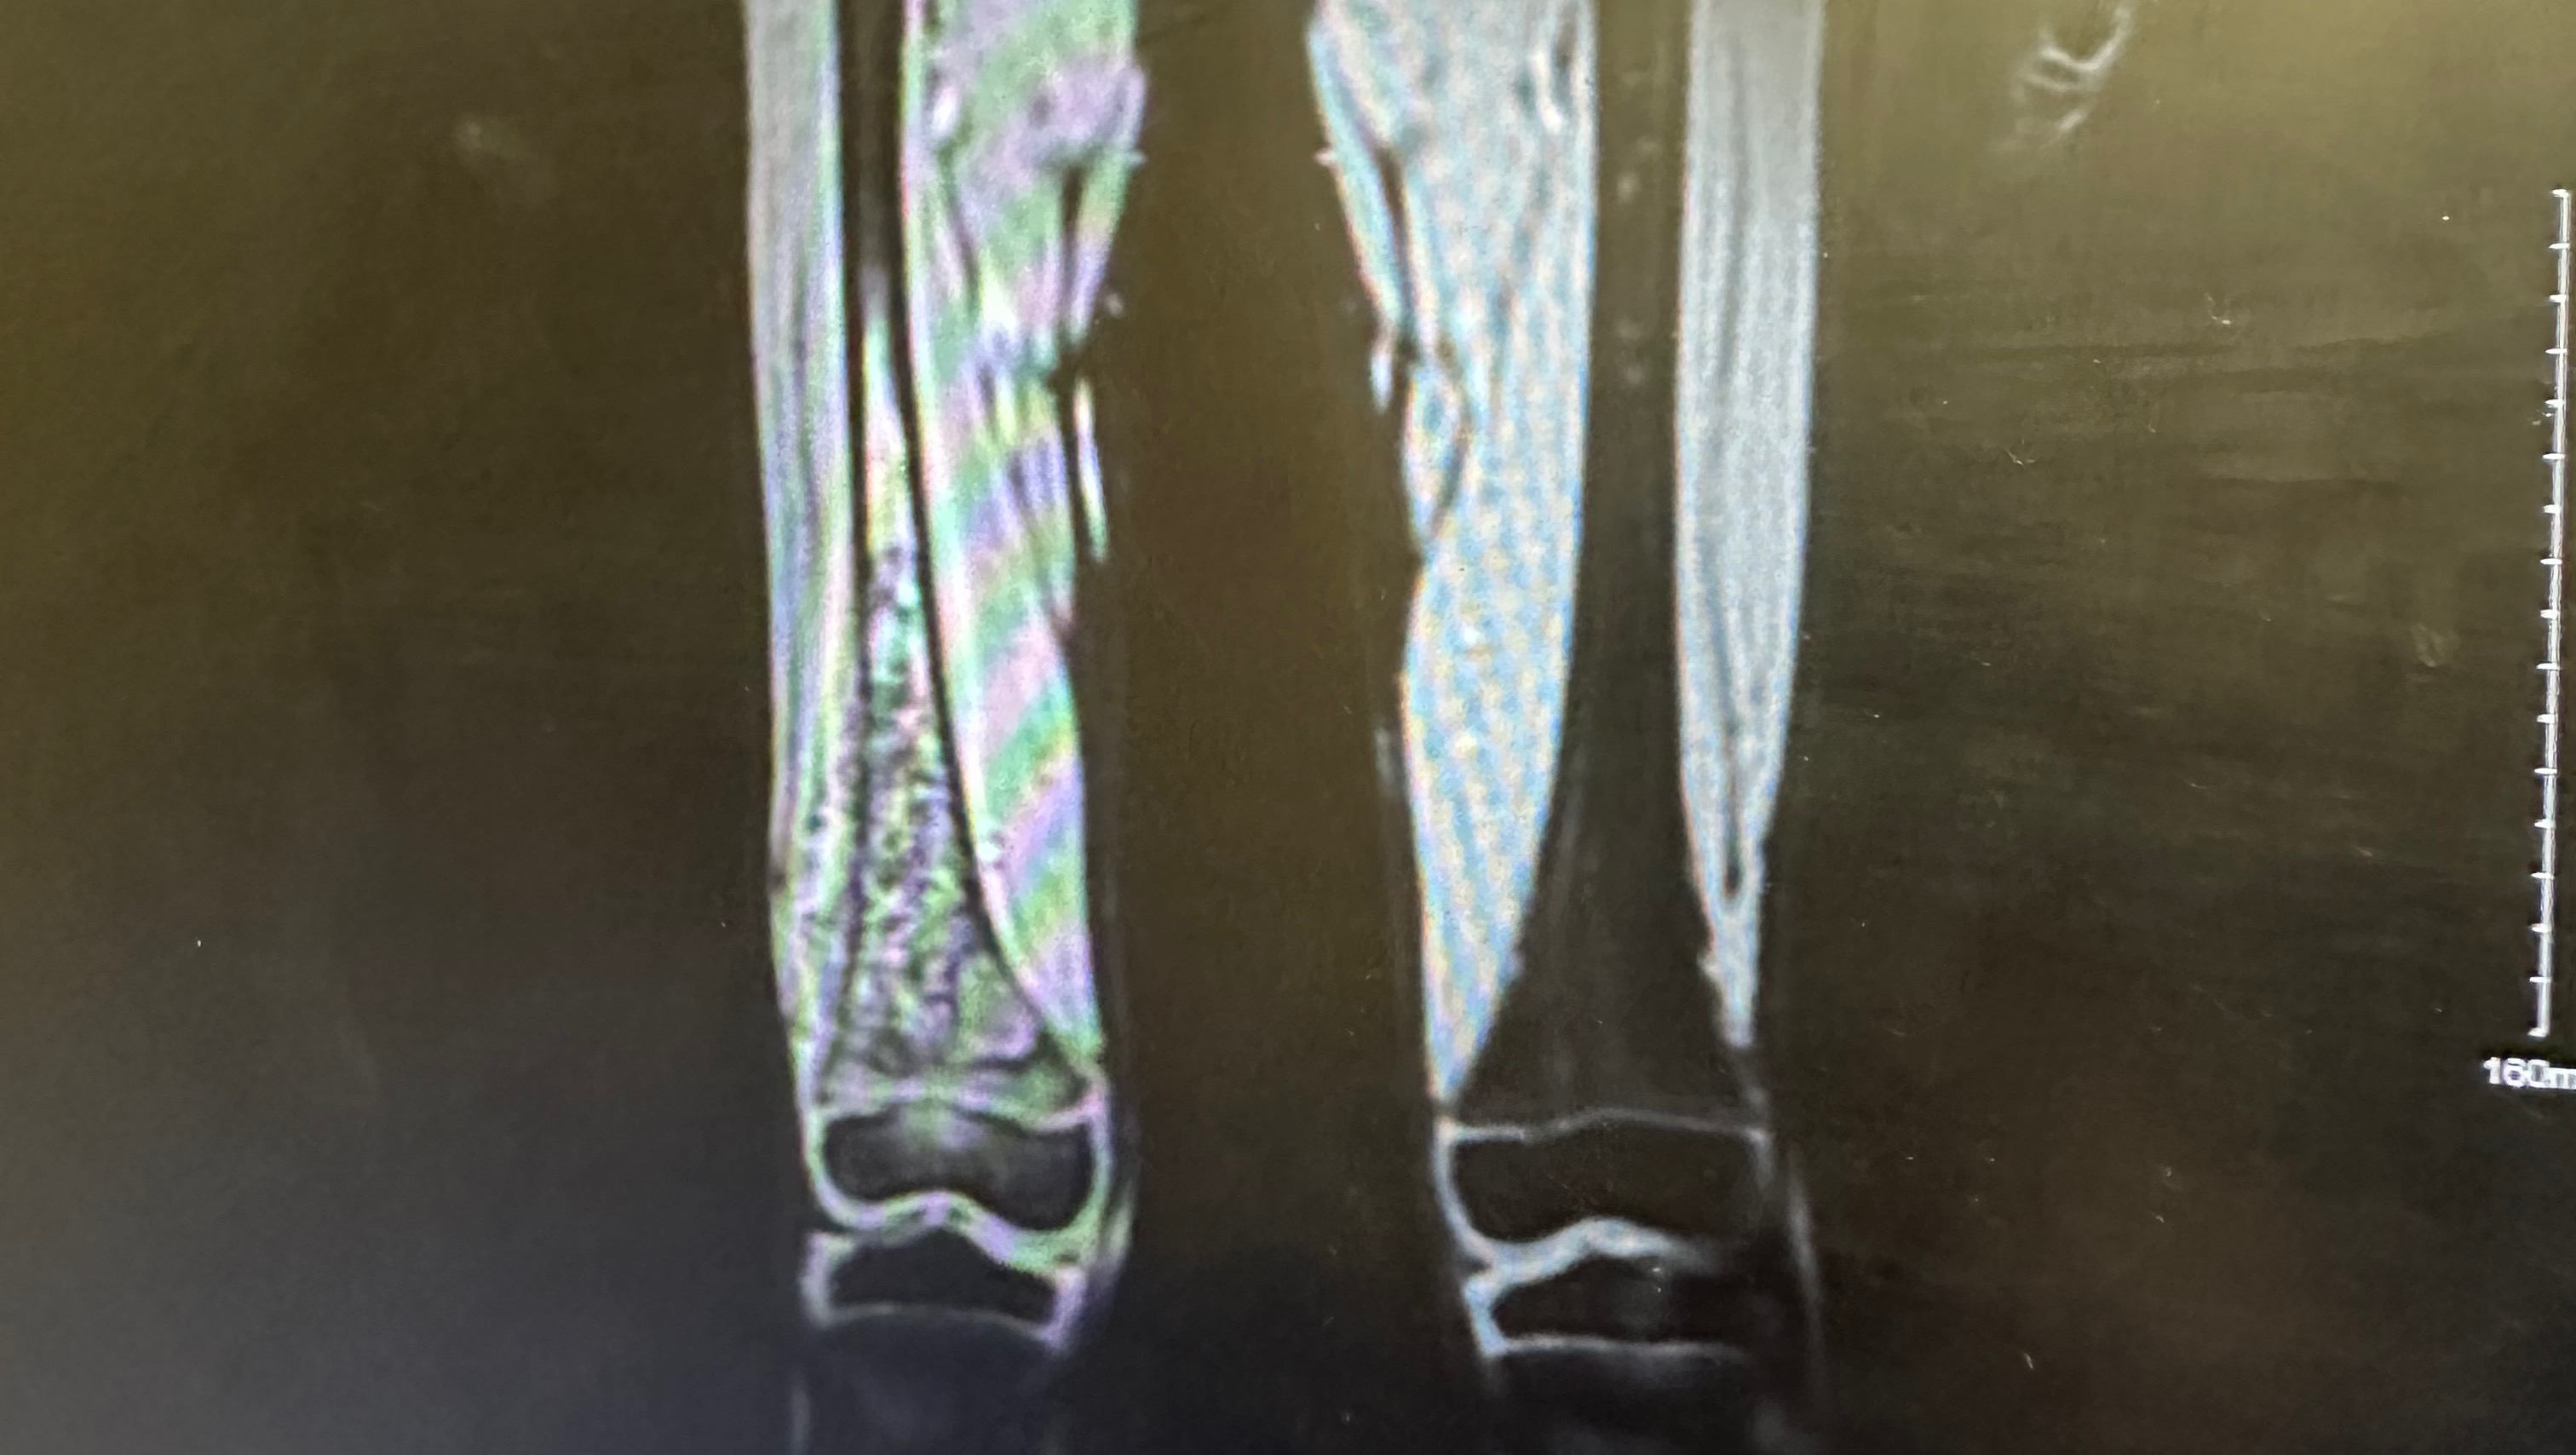

We were sent to Peoria for an MRI, and with that MRI we have been told they believe that this is osteosarcoma , the most painful cancer.